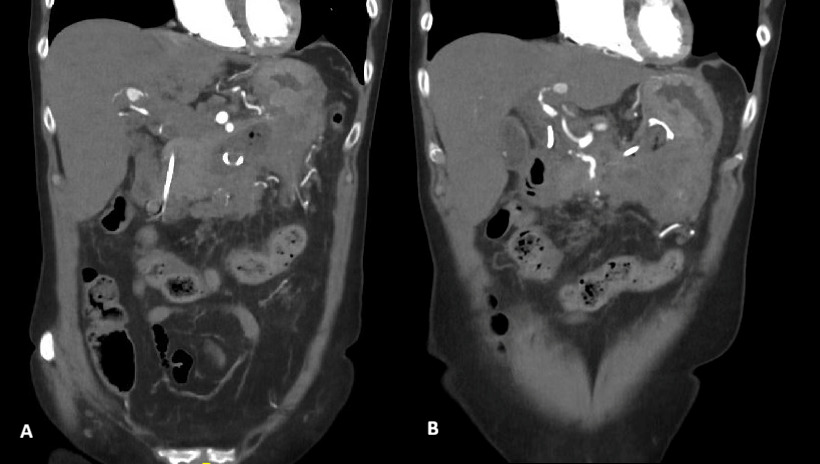

Further evaluation with Doppler ultrasound demonstrated non-occlusive bland thrombus within the common hepatic and left hepatic arteries. A subsequent CT angiogram (CTA), performed four weeks after the initial CT, confirmed the presence of multiple visceral pseudoaneurysms involving the hepatic arterial system. These included aneurysms of the right hepatic artery measuring 5.5 mm and 5.8 mm, intermediate hepatic artery aneurysms measuring 7.7 mm, 5.7 mm, and 14 mm, and a left hepatic artery aneurysm measuring 10.4 mm. Additionally, the coeliac trunk appeared diffusely aneurysmal with associated luminal irregularity (figure 3). All aneurysms demonstrated interval enlargement compared with prior imaging (Figure 2). Notably, during this period, the patient’s inflammatory markers and liver function tests had normalised.

Two weeks later, a repeat CTA demonstrated interval resolution of the previously identified pseudoaneurysms arising from the right, intermediate, and left hepatic arteries. The right and intermediate hepatic arteries were of markedly reduced calibre and tapered shortly after their origins, suggesting proximal arterial occlusion. The absence of contrast opacification within the previously visualised aneurysms was attributed to occlusion of the feeding vessels. Peripancreatic inflammatory stranding had mildly improved, and the previously noted lesser sac collection was no longer visualised (Figure 4).

_and_axial_(b)_ct_images_demonstrating_the_lack_of_contrast_in_and_soft_tissue_.png)

_and_.png)

_and_left_(b)_hepatic_arte.png)